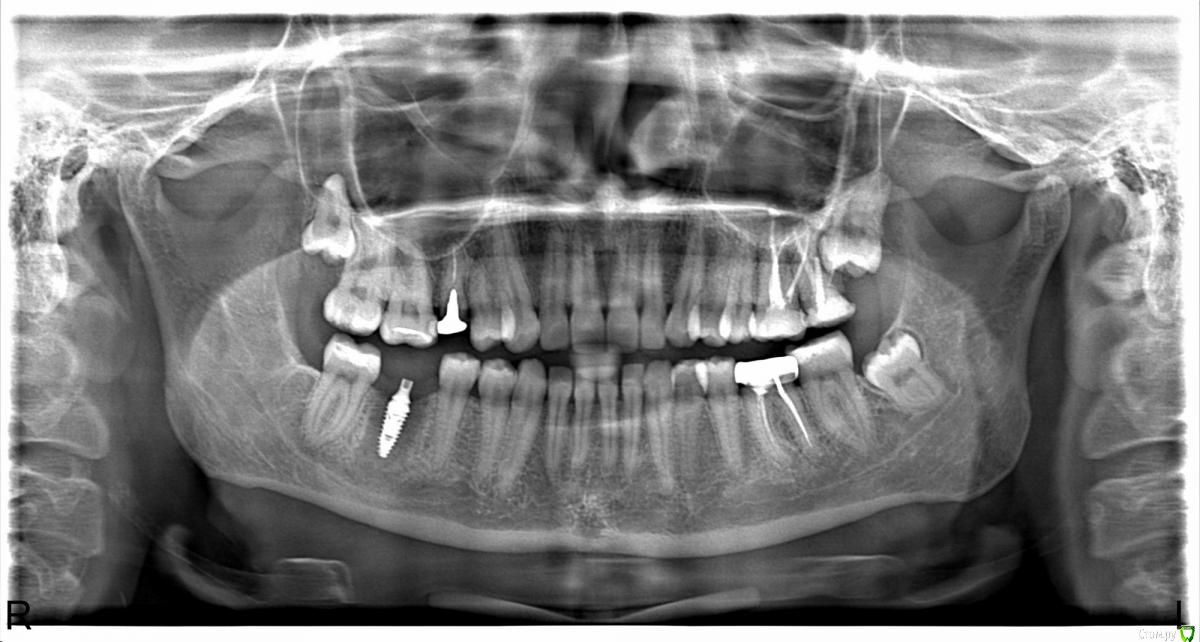

lepestochek Опубликовано 5 ноября, 2015 Поделиться Опубликовано 5 ноября, 2015 (изменено) Здравствуйте! Хотелось бы услышать профессиональную оценку по поводу жевательного зуба 36. Более 10 лет на нём стояла коронка. На снимке врач увидел воспаление у корня и предложил протезирование коронкой из диоксида циркония и, вероятно, вкладка( точно скажет на следующем приёме), предварительно пролечив каналы. После чего воспаление должно со временем исчезнуть. Коронку сняли( фото). На внутренней стороне нет стенки, поэтому хотелось бы знать надёжно ли будет предложенное лечение. А если и возможно, то нельзя ли металлокерамической коронкой накрыть? 15 зуб подготовили под культевую вкладку из кобальт хрома и коронки из диоксида циркония, так как металлокерамика сказали не будет держаться. И это немалые деньги. Ещё раз прошу, подскажите, стоит ли 36 зуб таких затрат? Спасибо. Изменено 5 ноября, 2015 пользователем lepestochek Ссылка на комментарий

IvanK Опубликовано 6 ноября, 2015 Поделиться Опубликовано 6 ноября, 2015 36 я бы удалил 4 Ссылка на комментарий

Larnary Опубликовано 6 ноября, 2015 Поделиться Опубликовано 6 ноября, 2015 Цельноциркон будет стачивать антагонисты. Я бы в данной ситуации выделил 2 главных момента:-на сколько глубоко под десну разрушена язычная стенка. По таким фото можно только гадать.-успешность эндодонтического лечения. Ссылка на комментарий